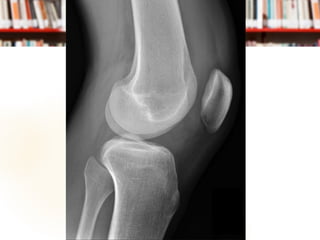

 Film Knee AP, Lateral

Management at ER Film Knee AP, Lateral